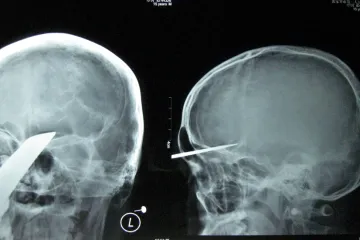

Čínskému chlapci vyoperovali z hlavy meč

Peking – Čínští chirurgové úspěšně dostali z hlavy patnáctiletého chlapce půlmetrový meč. Čang Pin pozval k sobě domů skupinu svých vrstevníků. Jeden z jeho kamarádů přitom přinesl japonský meč. Když si pak se zbraní hráli, najednou se meč zabodl Čangovi přímo mezi oči.